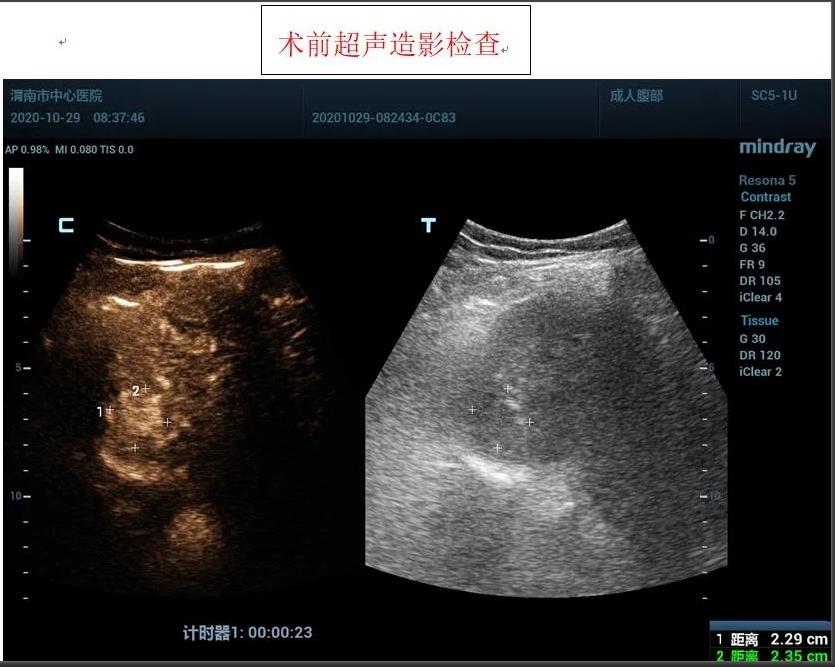

患者女性,71岁,因“糖尿病、肝硬化”在外院进行治疗,住院前进行常规检查,发现肝脏占位性病变,为进一步诊治前来我院,入住感染性疾病科,为进一步明确肝脏肿瘤性质,为患者进行超声造影检查,根据超声造影血流灌注情况,提示肝脏右前叶上段肝细胞癌可能。

患者肿瘤较小且位置较深,紧贴膈肌,且患者伴有冠心病、糖尿病等基础性疾病,感染科李红兵主任在充分评估患者状况后,与超声科刘晓晖主任进行细致讨论,决定对患者行超声引导下微波消融术,因病灶位置特殊,为减少手术风险,特邀西京医院王建宏教授前来进行指导,借助超声造影对肿瘤的部位和血供进行评估和确认后,华玺副主任医师在超声引导下穿刺取活检(病理结果为肝细胞癌)、布针、将消融针娴熟准确地刺入肿块,对肿块进行灭活治疗。

据超声科刘晓晖主任介绍,超声造影技术联合微波消融术可以在术前更明确的反映肿瘤病灶的实际大小及其浸润范围,可将微波治疗范围以超声造影测值作为参考,从而更客观的判断肿瘤病灶大小及周围浸润情况,确认需治疗的范围,同时可以使用超声造影在微波消融术中进行检测引导,术后通过超声造影确认肿瘤是否完全灭活。该方法与传统外科手术相比创伤小,手术时间短,术中痛苦小,并发症极少;术后恢复快,缩短了住院时间,乐鱼手机站入口超声科将超声造影技术与微波消融术联合使用,为患者带来了新的治疗希望。